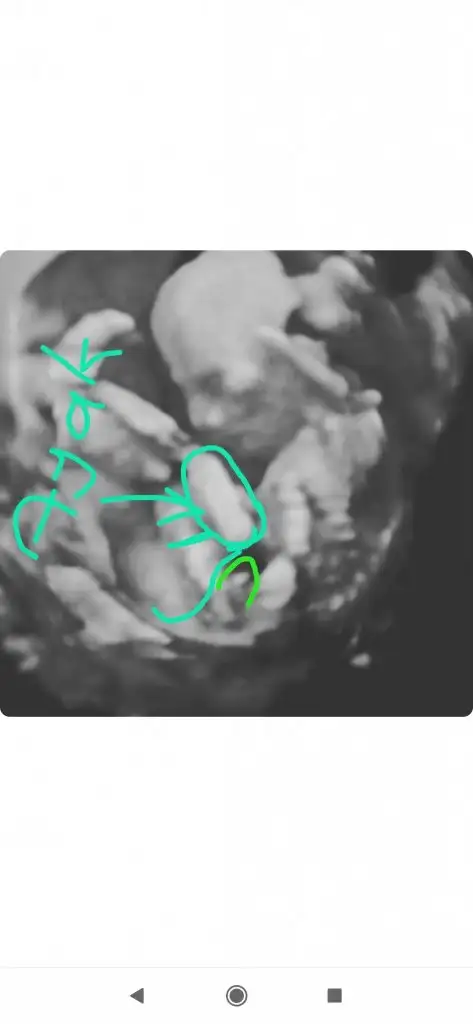

Ben de kız demistim .o haftalik ultrason kaginda daha belli oluyor cinciyet tahmini.çıkınti paralel oldugu icin kız demistim ben de.buradaki fotoda net belli sizin.seni çok iyi anlıyorum.benim de iki kızım var.ve ücuncuyu istiyoruz.olmadi 5 aydir gebelik.hayırlısı olsun.saglikli olsun en önemlisi.Rabbimin vardır bildiği .verdiyse en hayırlısını vermistir.gönlünü ferah tut .Evet Dr söyledi teşekkürlerEki Görüntüle 2764435

Ama çoğu kişi erkek bu bebek diyorBen de kız demistim .o haftalik ultrason kaginda daha belli oluyor cinciyet tahmini.çıkınti paralel oldugu icin kız demistim ben de.buradaki fotoda net belli sizin.seni çok iyi anlıyorum.benim de iki kızım var.ve ücuncuyu istiyoruz.olmadi 5 aydir gebelik.hayırlısı olsun.saglikli olsun en önemlisi.Rabbimin vardır bildiği .verdiyse en hayırlısını vermistir.gönlünü ferah tut .

Ben de kız demistim .o haftalik ultrason kaginda daha belli oluyor cinciyet tahmini.çıkınti paralel oldugu icin kız demistim ben de.buradaki fotoda net belli sizin.seni çok iyi anlıyorum.benim de iki kızım var.ve ücuncuyu istiyoruz.olmadi 5 aydir gebelik.hayırlısı olsun.saglikli olsun en önemlisi.Rabbimin vardır bildiği .verdiyse en hayırlısını vermistir.gönlünü ferah tut .

Ben cizmedim isegramdan bu sayfa çizdi cinsiyetini öğren diye bi sayfaSen ustunu cizmissin bilemedim simdi.baska bir dr a da gitsen imkanın vaktin varsa için rahat olur .

Evet o sayfa bana erkek dedi bugün öğrenmeye gideceğim bende hayırlısı olsunBen cizmedim isegramdan bu sayfa çizdi cinsiyetini öğren diye bi sayfa